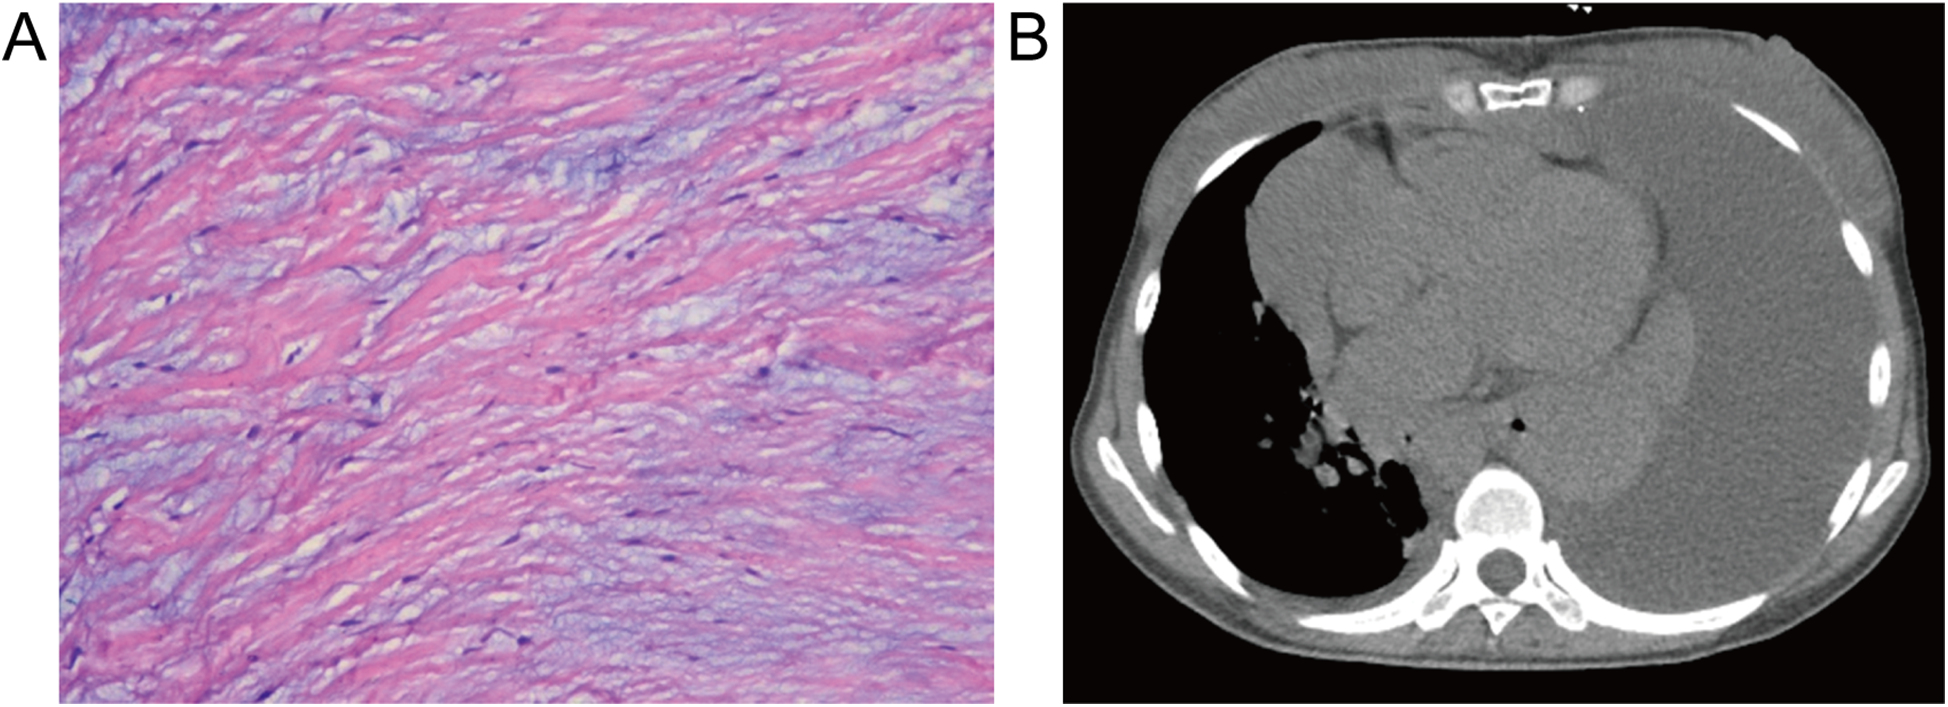

Following the diagnostic workup, the patient underwent routine aortic valve replacement surgery, confirming a BAV with leaflet thickening, severe aortic regurgitation no calcification, no adhesion, and aortic ring dilatation. The diseased valve was replaced with a prosthetic valve. Pathological examination showed fibrous tissue hyperplasia with hyaline and myxoid degeneration (Figure 2A). Chest CT eleven days post-surgery revealed large left-sided pleural and pericardial effusions (Figure 2B), requiring thoracentesis and pericardiocentesis, which drained chylous fluid and hematoma, respectively. The patient's symptoms subsequently improved, and she was discharged. However, she presented again shortly thereafter with a large pleural effusion, requiring thoracic duct ligation. Follow-up chest CT at 10 months showed a small residual pleural effusion.

Figure 2

Histopathological and postoperative imaging findings. (A) Resected aortic valve demonstrating fibrous tissue hyperplasia with hyaloid and mucoid degeneration (hematoxylin-eosin stain, ×100). (B) Postoperative mediastinum CT revealing a large pleural effusion and pericardial effusion in the left thorax and pericardium.